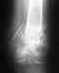

имеется ли подвывих и нужна ли стяжка?

женщине была сделана операция пластина 29 ноября, был перелом большеберцовой кости. Сейчас женщина наблюдается в другой больнице и там по снимкам сказали есть подвывих, который не был устранен. Подскажите есть ли подвывих и требуется ли повторная операция?